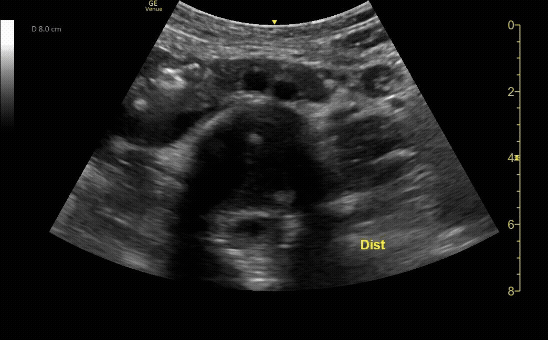

Distal transverse (short) view demonstrating the bifurcation. Measure anterior-to-posterior proximally. Should measure <3cm and taper distally.

c/o Taylor Wahrenbrock, MD